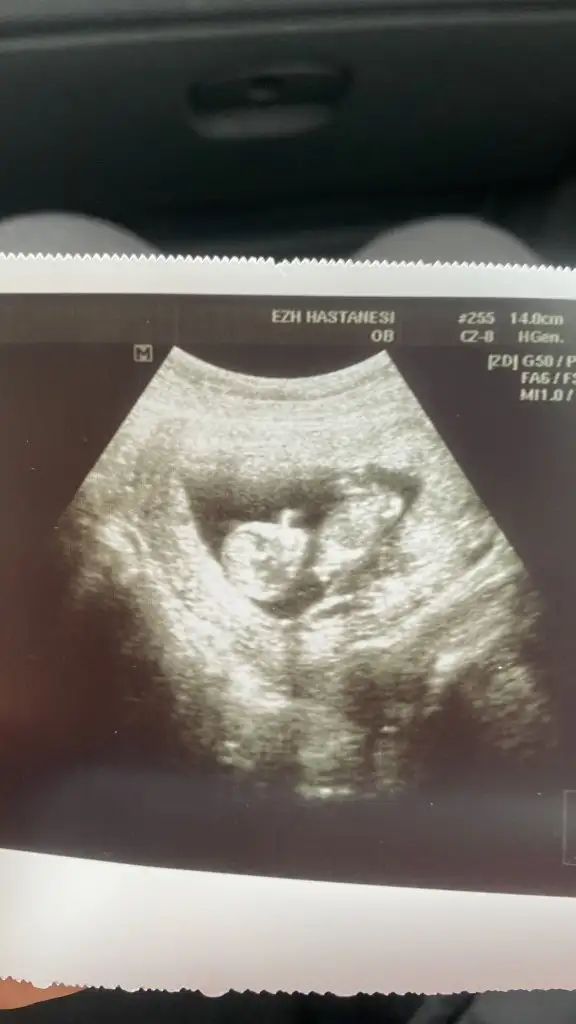

Merhaba banada yorum da yapabilirmisiniz çok merak ediyorum

• IMG_0748.webp

IMG_0748.webp

27,1 KB · Görüntüleme: 52

• IMG_0753.webp

IMG_0753.webp

21,8 KB · Görüntüleme: 50